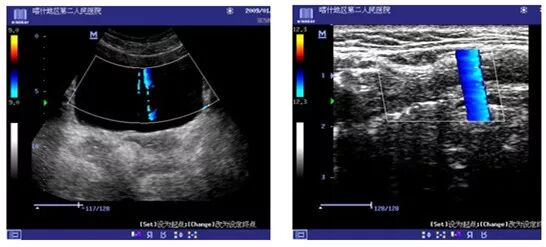

2、超声设备接收模块故障引起的干扰(DC-6)

现象:上图干扰会有规律的从左到右滚动

原因:模拟接收通道器件损坏

处理措施:更换放大板